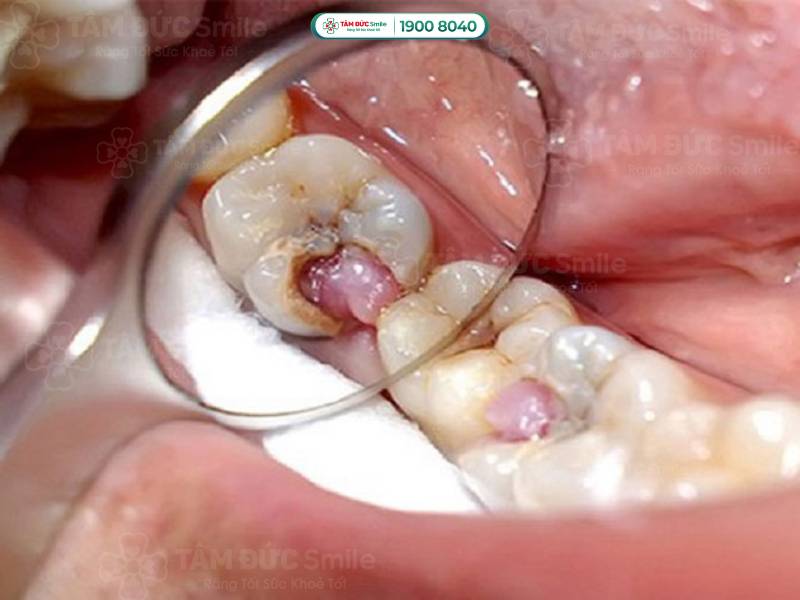

Răng sâu lồi thịt là răng đã viêm nhiễm nặng, lỗ sâu lớn nên vi khuẩn xâm nhập vào tủy răng. Phần niêm mạc bị sưng lên gây đau đớn, nhất là khi ăn nhai. Khi đánh răng hoặc chạm vào vùng răng bị sâu, Quý khách có thể thấy tia máu hoặc phần bọt đánh răng có máu đỏ.

1.1.4. Răng sâu lồi thịt gây biến chứng viêm nhiễm sâu dưới răng

Khi răng bị sâu, vi khuẩn xâm nhập vào bên trong răng và hình thành vùng viêm nhiễm. Nếu không được điều trị, viêm nhiễm lan rộng xuống chân răng, gây viêm tủy răng và viêm nha chu. Trong trường hợp nặng hơn, tình trạng viêm sinh ra mủ, tạo thành áp xe, gây đau nhức dữ dội.